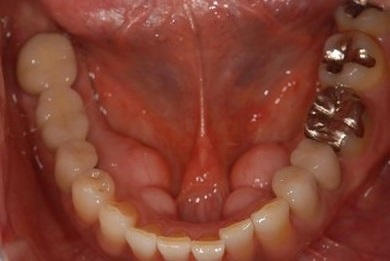

骨再生インプラント治療+セラミック治療+歯肉歯槽骨整形手術

| 治療内容 | インプラント2本(ソケットリフト、GBR)、メタルボンドセラミッククラウン3本、歯肉歯槽骨整形手術 | ||||||||||||||||||||||||||||||||